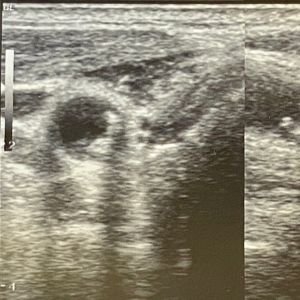

Umbilical Cord Blood Flow Assessment

This Fetal Doppler scan evaluates the blood flow through the umbilical cord, helping detect potential issues such as placental insufficiency that could affect fetal health.